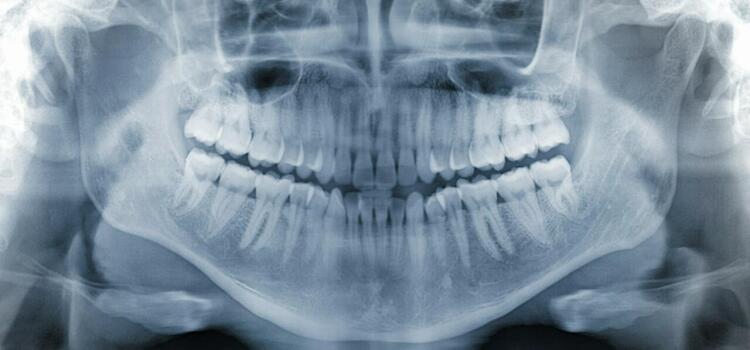

Pracownia RTG Profim specjalizuje się w rentgenodiagnostyce twarzoczaszki. Badania wykonywane są przede wszystkim na potrzeby diagnostyki stomatologicznej i laryngologicznej. Pacjenci poddają się im ze względu na konieczność leczenia chirurgicznego, zachowawczego, ortodontycznego i protetycznego. Aparatura używana w pracowni umożliwia m.in. wykonywanie badań RTG zewnątrzustnych i wewnątrzustnych. Diagnostyka zewnątrzustna to:

-zdjęcia pantomograficzne,

-zdjęcia stawów skroniowo-żuchwowych,

-zdjęcia cefalometryczne,

-zdjęcia zatok,

Przykładem zdjęć wewnątrzustnych wykonywanych w pracowni są zdjęcia punktowe zęba, skrzydłowo-zgryzowe i zgryzowe.